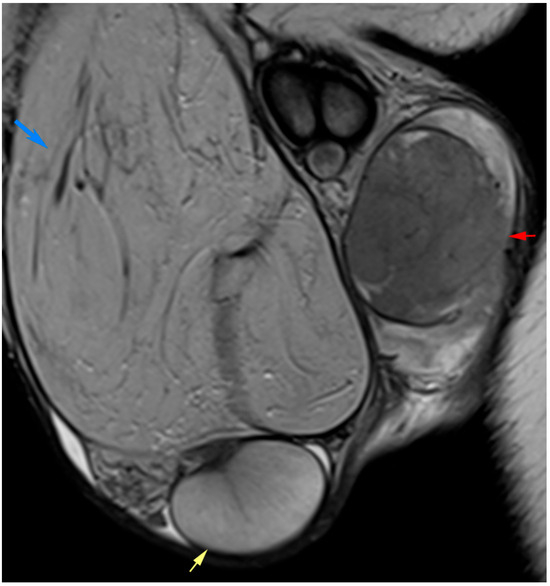

MRI of the Scrotum and Penis: Current Applications and Clinical Relevance

Background: Magnetic resonance imaging (MRI) plays an increasingly important role in the evaluation of scrotal and penile disorders, complementing ultrasonography in cases where findings are equivocal or complex. With its superior soft-tissue contrast, multiplanar capability, and advanced functional sequences, MRI provides unparalleled anatomic and tissue characterization across a wide range of male genital pathologies. Summary: This review summarizes current clinical applications of MRI in scrotal and penile imaging and discusses its diagnostic value, protocol optimization, and interpretive features. In scrotal pathology, MRI accurately differentiates torsion, trauma, infection, and neoplasms, aiding in the distinction between benign and malignant testicular lesions and supporting testis-sparing management. Quantitative diffusion and perfusion metrics further refine lesion characterization. In andrology, MRI biomarkers such as apparent diffusion coefficient (ADC), magnetization transfer ratio (MTR), and proton spectroscopy serve as promising non-invasive indicators of spermatogenic activity in male infertility. In penile imaging, MRI enables precise local staging of carcinoma, assessment of plaque morphology and activity in Peyronie’s disease, evaluation of tissue viability in priapism, and detection of prosthesis-related complications. Conclusions: MRI has become an essential problem-solving tool in the assessment of scrotal and penile diseases, enhancing diagnostic confidence and surgical planning. Future directions include protocol standardization, quantitative parameter validation, and the integration of radiomics and artificial intelligence to improve reproducibility and clinical impact. Full article

Figure 1